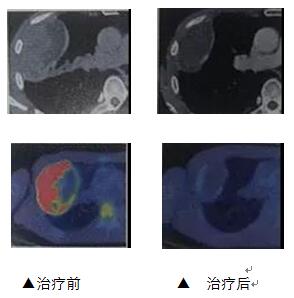

治疗前后影像对比

治疗效果:

治疗前的PDG-PET内显示积累的红色在温热化疗与放射线治疗后消失。肿瘤切除后,病理组织标本显示无癌细胞存在。

案例2:大肠癌肝转移

原发灶切除后。每周一次使用化学疗法和温热疗法,共计8次。

治疗开始2个月后的CT显示,肝转移灶几乎消失。